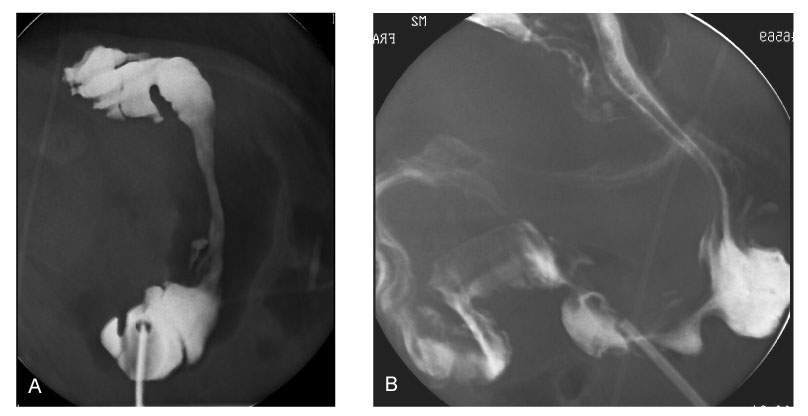

Fig. 1

Simple abdominal X-ray film shows severe kyphosis and ventriculo-peritoneal shunt catheter in the abdomen. Normal intestinal gas pattern is seen.

Fig. 1 Simple abdominal X-ray film shows severe kyphosis and ventriculo-peritoneal shunt catheter in the abdomen. Normal intestinal gas pattern is seen.